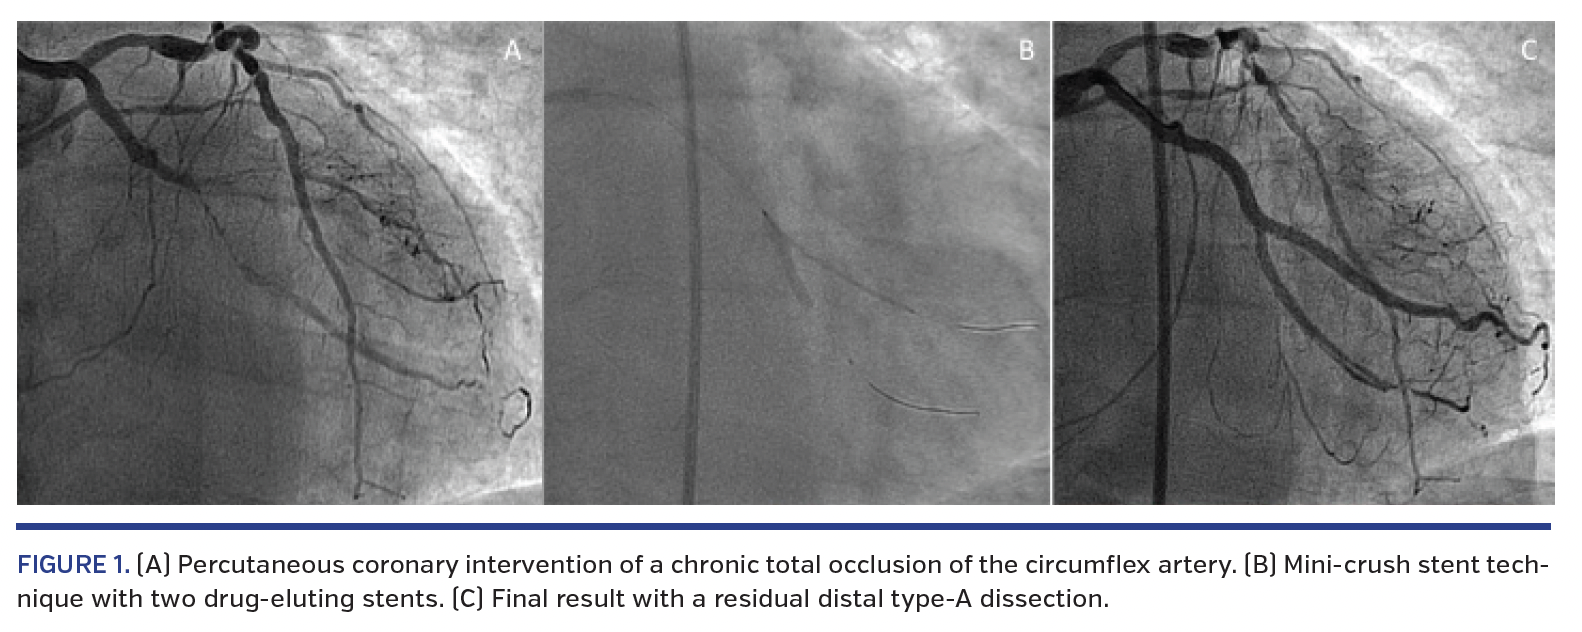

A 53-year-old man underwent percutaneous coronary intervention (PCI) of a chronic total occlusion (CTO) of the circumflex artery (Figure 1A). A mini-crush stent technique with two drug-eluting stents (DESs) was performed (Figure 1B). Another overlapped DES was implanted proximally, with good final result despite a residual distal type-A dissection (Figure 1C). Six-month follow-up imaging showed a completely sealed distal vessel and a coronary artery aneurysm (CAA) (Figure 1D, arrow) near the site of the overlapped stents (Figure 1E, arrowhead). Optical coherence tomography demonstrated a true, small, fusiform, type-IV CAA with homogeneous, signal-rich luminal surface (Figure 1E). The struts at the CAA had no endothelial coverage (Figure 1E, asterisk). Struts located at the rest of the circumference and immediately proximal to the CAA were well covered (Figure 1F, asterisk). Conservative management and indefinite dual-antiplatelet therapy was decided. At 9 months, the patient remained asymptomatic. CAAs have been rarely described after DES implantation.1,2 The underlying pathophysiology remains unknown. In our case, several mechanisms could be involved. First, the vessel damage during initial PCI related to aggressive predilation and probable short subintimal wire passage. Second, the increased local drug delivery at the small area of the three overlapped stents, which could impair vessel healing. To the best of our knowledge, this is the first case of CAA affecting a bifurcated CTO treated with a two-stent technique.